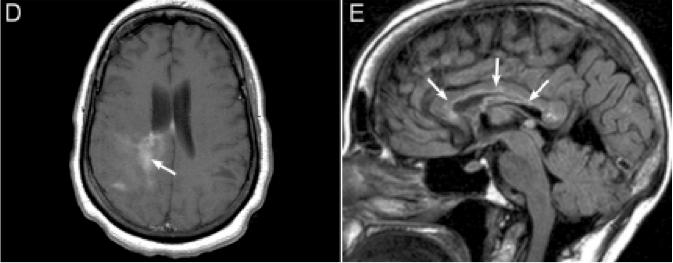

4. NMOSD 头MRI:丘脑、三脑室周围、锥体束和侧脑室周围等部位都可能出现片状、云雾状病灶